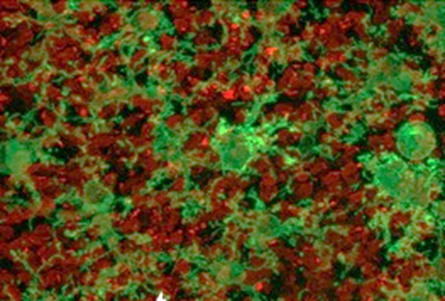

Immagine 1: micrografia a fluorescenza di una sezione della retina esterna. In rosso: i coni

Partendo da questa osservazione, il gruppo di ricerca ha esplorato una strada semplice ma nuova: riutilizzare farmaci antinfiammatori già noti, come il desametasone. Somministrando tale farmaco per via intraoculare in modelli preclinici di retinite pigmentosa, è stato osservato che le cellule visive (coni) e l’epitelio pigmentato, un tessuto fondamentale per il supporto della retina, si preservano dall’infiammazione.